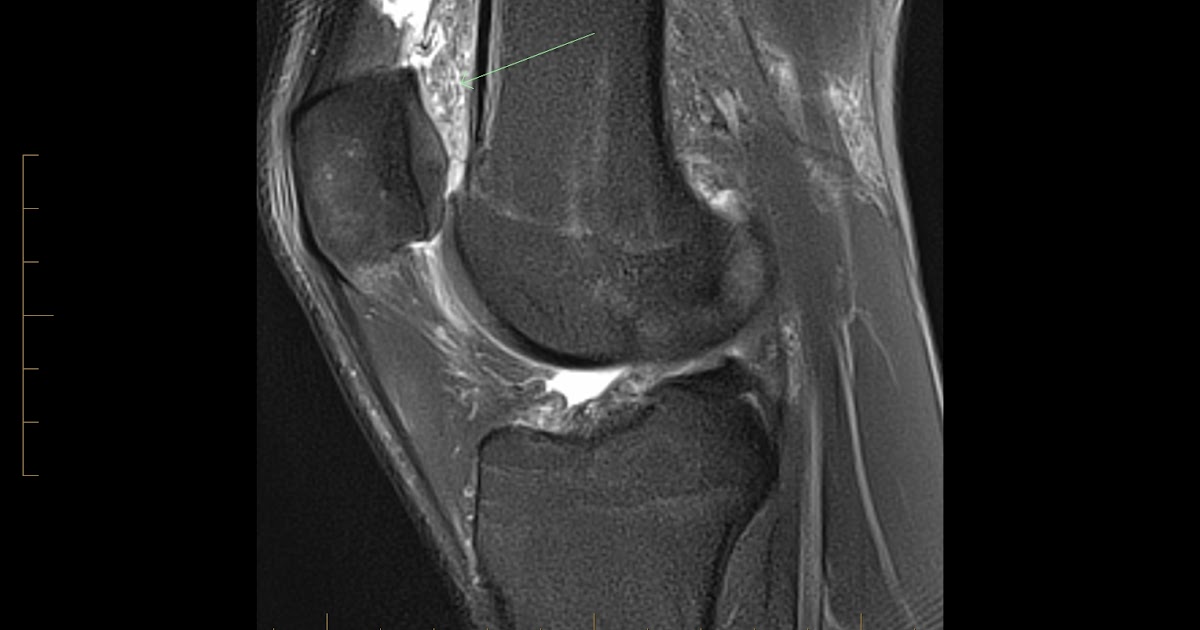

Quadriceps fatpad impingement syndrome MRI findings BMJ Case Reports

Quadriceps fatpad impingement syndrome MRI findings BMJ Case Reports Knee Fat Pad Injury Symptoms Activities that involve frequent bending or extending of the knee joint, such as. The pain is usually localised on either side of the kneecap, directly beneath it, or, occasionally, behind the patellar tendon. fat pad impingement is when your infrapatellar fat pad is pinched (impinged) between your kneecap and thigh bone or between your thigh bone and shin bone.. Knee Fat Pad Injury Symptoms.